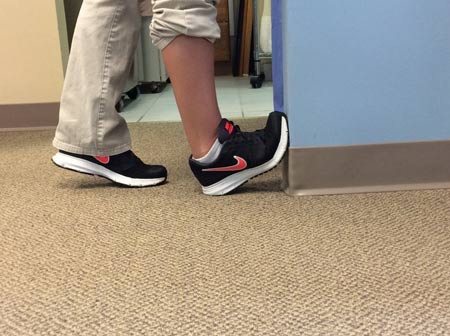

از پابرهنه بودن دوری کنید

جهت بهبودی درد پاشنه پا از پابرهنه بودن پا اکیداً خودداری کنید. همیشه باید کفشهایی را پوشید که دارای ارتزهای سفارشی ساخت هستند و گاهی نیز از محافظهای تجویزی طبی مخصوص قوس کف پا استفاده میشود تا روند ترمیم سریعتر انجام گیرد.

کفش مناسب به پا کنید

کفش خیلی صاف، خیلی مرتفع، خیلی نرم یا خیلی سفت میتواند درد پاشنه پا را تحریک کند. دکتر فیزیوتراپی بسته به شرایط شما توصیههایی را در اختیارتان قرار خواهد داد.